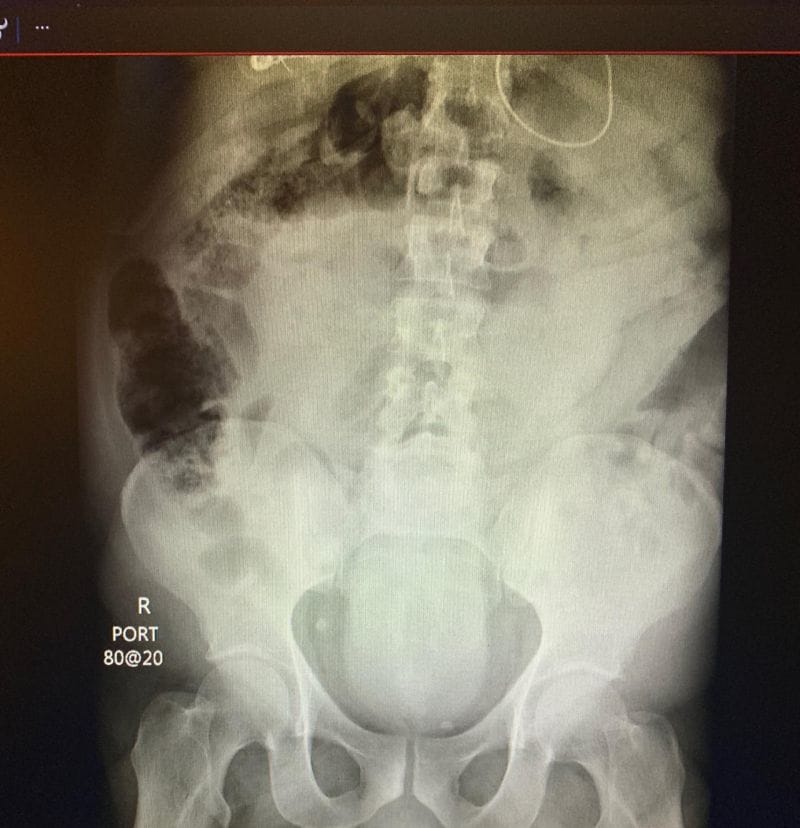

gif_animation ”オナニーの道具” がマンコから抜けなくなり、病院に搬送された女。無事取り出されたその大きさ、X線写真などが話題になっていた画像。(※ TOP画はイメージ)